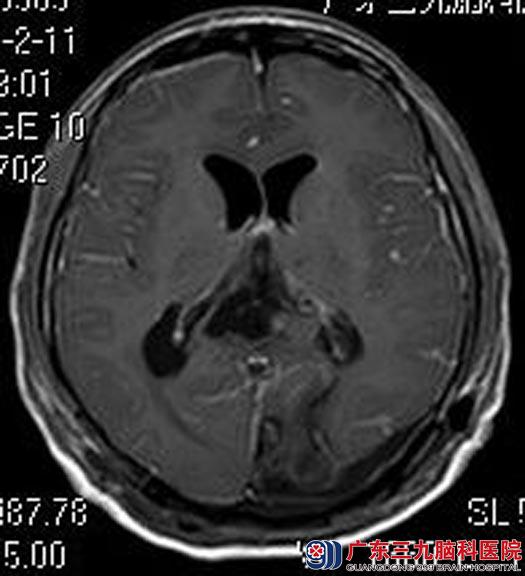

术前将肿瘤供血血管部分栓塞,然后由鲁明主任主刀,在全麻下行松果体区巨大脑膜瘤切除术,导航定位肿瘤范围,术中再次导航定位,术中见肿瘤呈红色,质中,血供丰富,边界清楚,有完整包膜,予镜下顺利将肿瘤全切。术后周先生神志清醒,头痛症状明显好转,四肢活动正常,无手术并发症。病理回报:过渡型脑膜瘤 WHO I级。

▲术后头颅MR